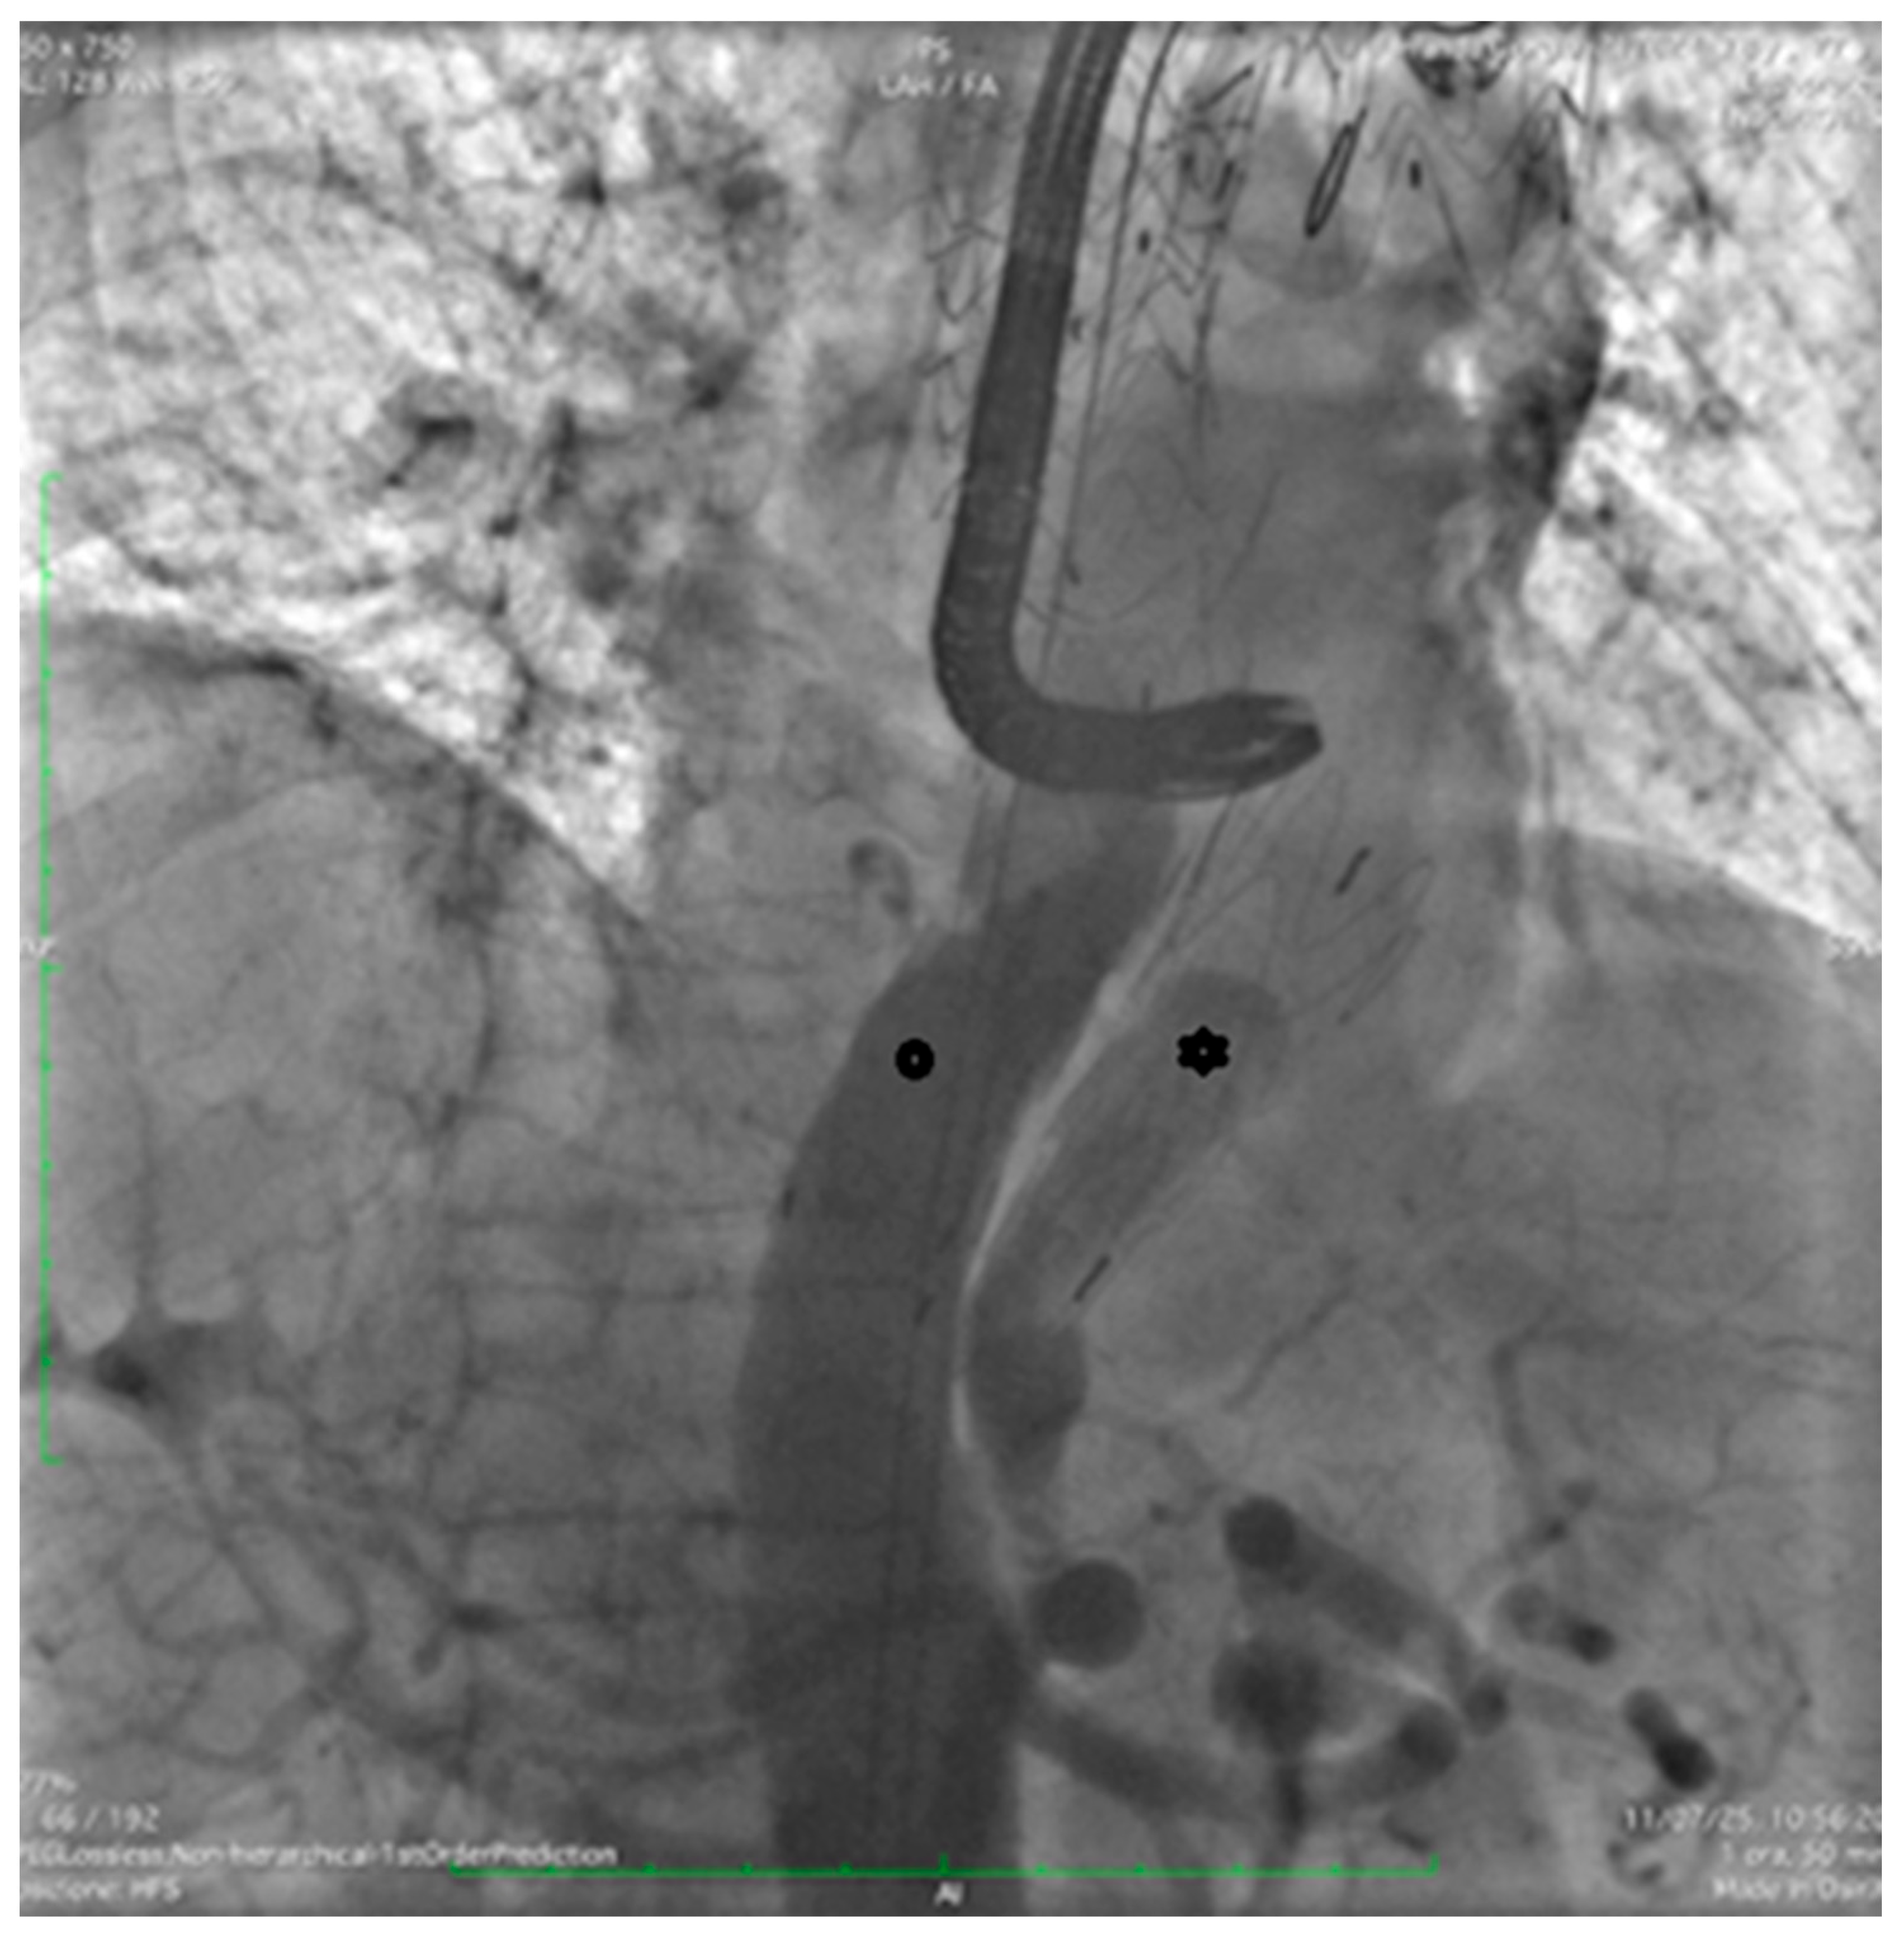

Finally, angiography confirmed proper device positioning, preserved visceral artery patency, and complete FL exclusion (Figure 5 and Figure 6).

Figure 5.

Final intraoperative angiography confirming the correct positioning of both the Terumo Aortic endograft (circle) and the FLOD (*).